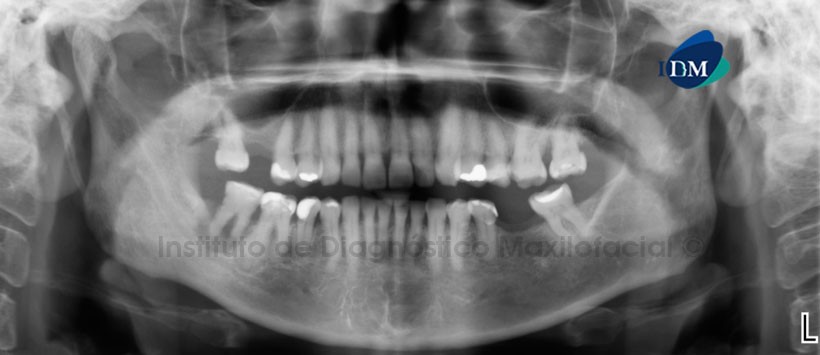

En la radiografía panorámica (Figura 1) se observa un proceso osteolítico peri-radicular en zona de pieza 47 con aumento de la densidad óseo circundante, así mismo se aprecia una imagen radiopaca proyectada a nivel de la raíz distal de la pieza 46.

A la evaluación de la tomografía volumétrica (CBCT) en los cortes axiales (Figura 2), coronales (Figura 3), transaxiales (Figura 4 y 5) y tangenciales (Figura 6), se aprecia una imagen hiperdensa ubicado a nivel peri-radicular de la raíz distal de la pieza 4.6, rodeado por un halo radiolúcido y un borde corticalizado, se aprecia además falta de definición del espacio periodontal y lámina dura. A nivel de la pieza 46, se evidencia una imagen hipodensa peri-radicular con marcado incremento de la densidad ósea circundante, que ocasiona erosión de la tabla ósea lingual sugerente de trayecto fistulosos.

En las reconstrucciones 3D se observan con detalle lla alteración patológica a nivel de la raiz distal de pieza 4.6, así como la lesión osteolítica a nivel de pieza 4.7 y la erosión de la tabla ósea lingual (Figura 7,8,9 y 10).

Conclusión: Signos tomográficos sugerentes de Cementoblastoma benigno infectado en pieza 4.6 y Absceso periodontal en pieza 4.7